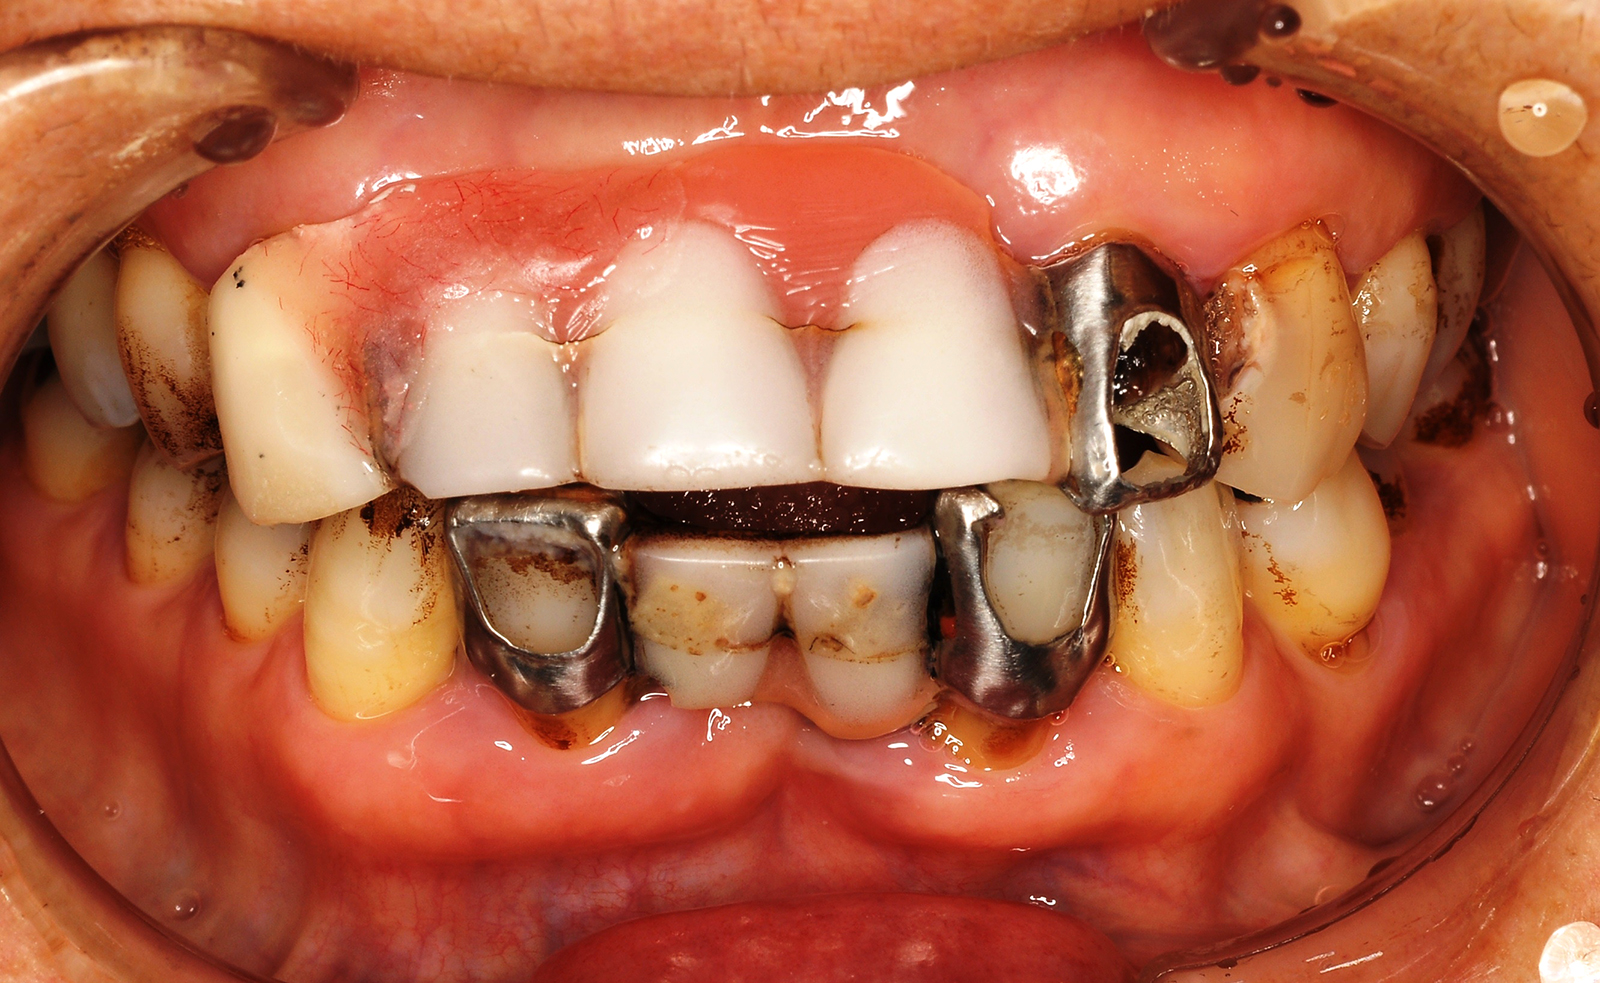

歯周病が重度に進行すると、歯を支える骨が溶けてしまうことがあります。その結果、支えを失った歯は通常の噛み合わせでの負荷を受け止めきれず、異常な方向に動いてしまうことがあります。

ここまでの状態になってしまうと、通常の歯周病治療だけでは対処が難しくなります。そこで当院では、歯周病治療と矯正治療を組み合わせた「歯周矯正治療」を行い、歯と歯茎の状態を改善しています。

歯周病が重度に進行すると、歯を支える骨が溶けて歯がぐらついてきます。この状態のままだと自然と歯が抜けてしまうことから抜歯を選択する歯科医院もあります。しかし、抜歯せずとも骨が再生し歯が安定すれば歯が抜けてしまうことはありません。

歯周病が進行すると歯周ポケットが深くなってしまい、通常の処置では歯石を取り除くことが難しくなります。この状態のまま放置してしまうと歯周病はさらに悪化し、歯が抜けるのも時間の問題となります。

この状態に対して有用なのが「歯周外科治療」です。歯肉を外科的に切開するなどして、深い部分に付着した歯石を取り除いていきます。